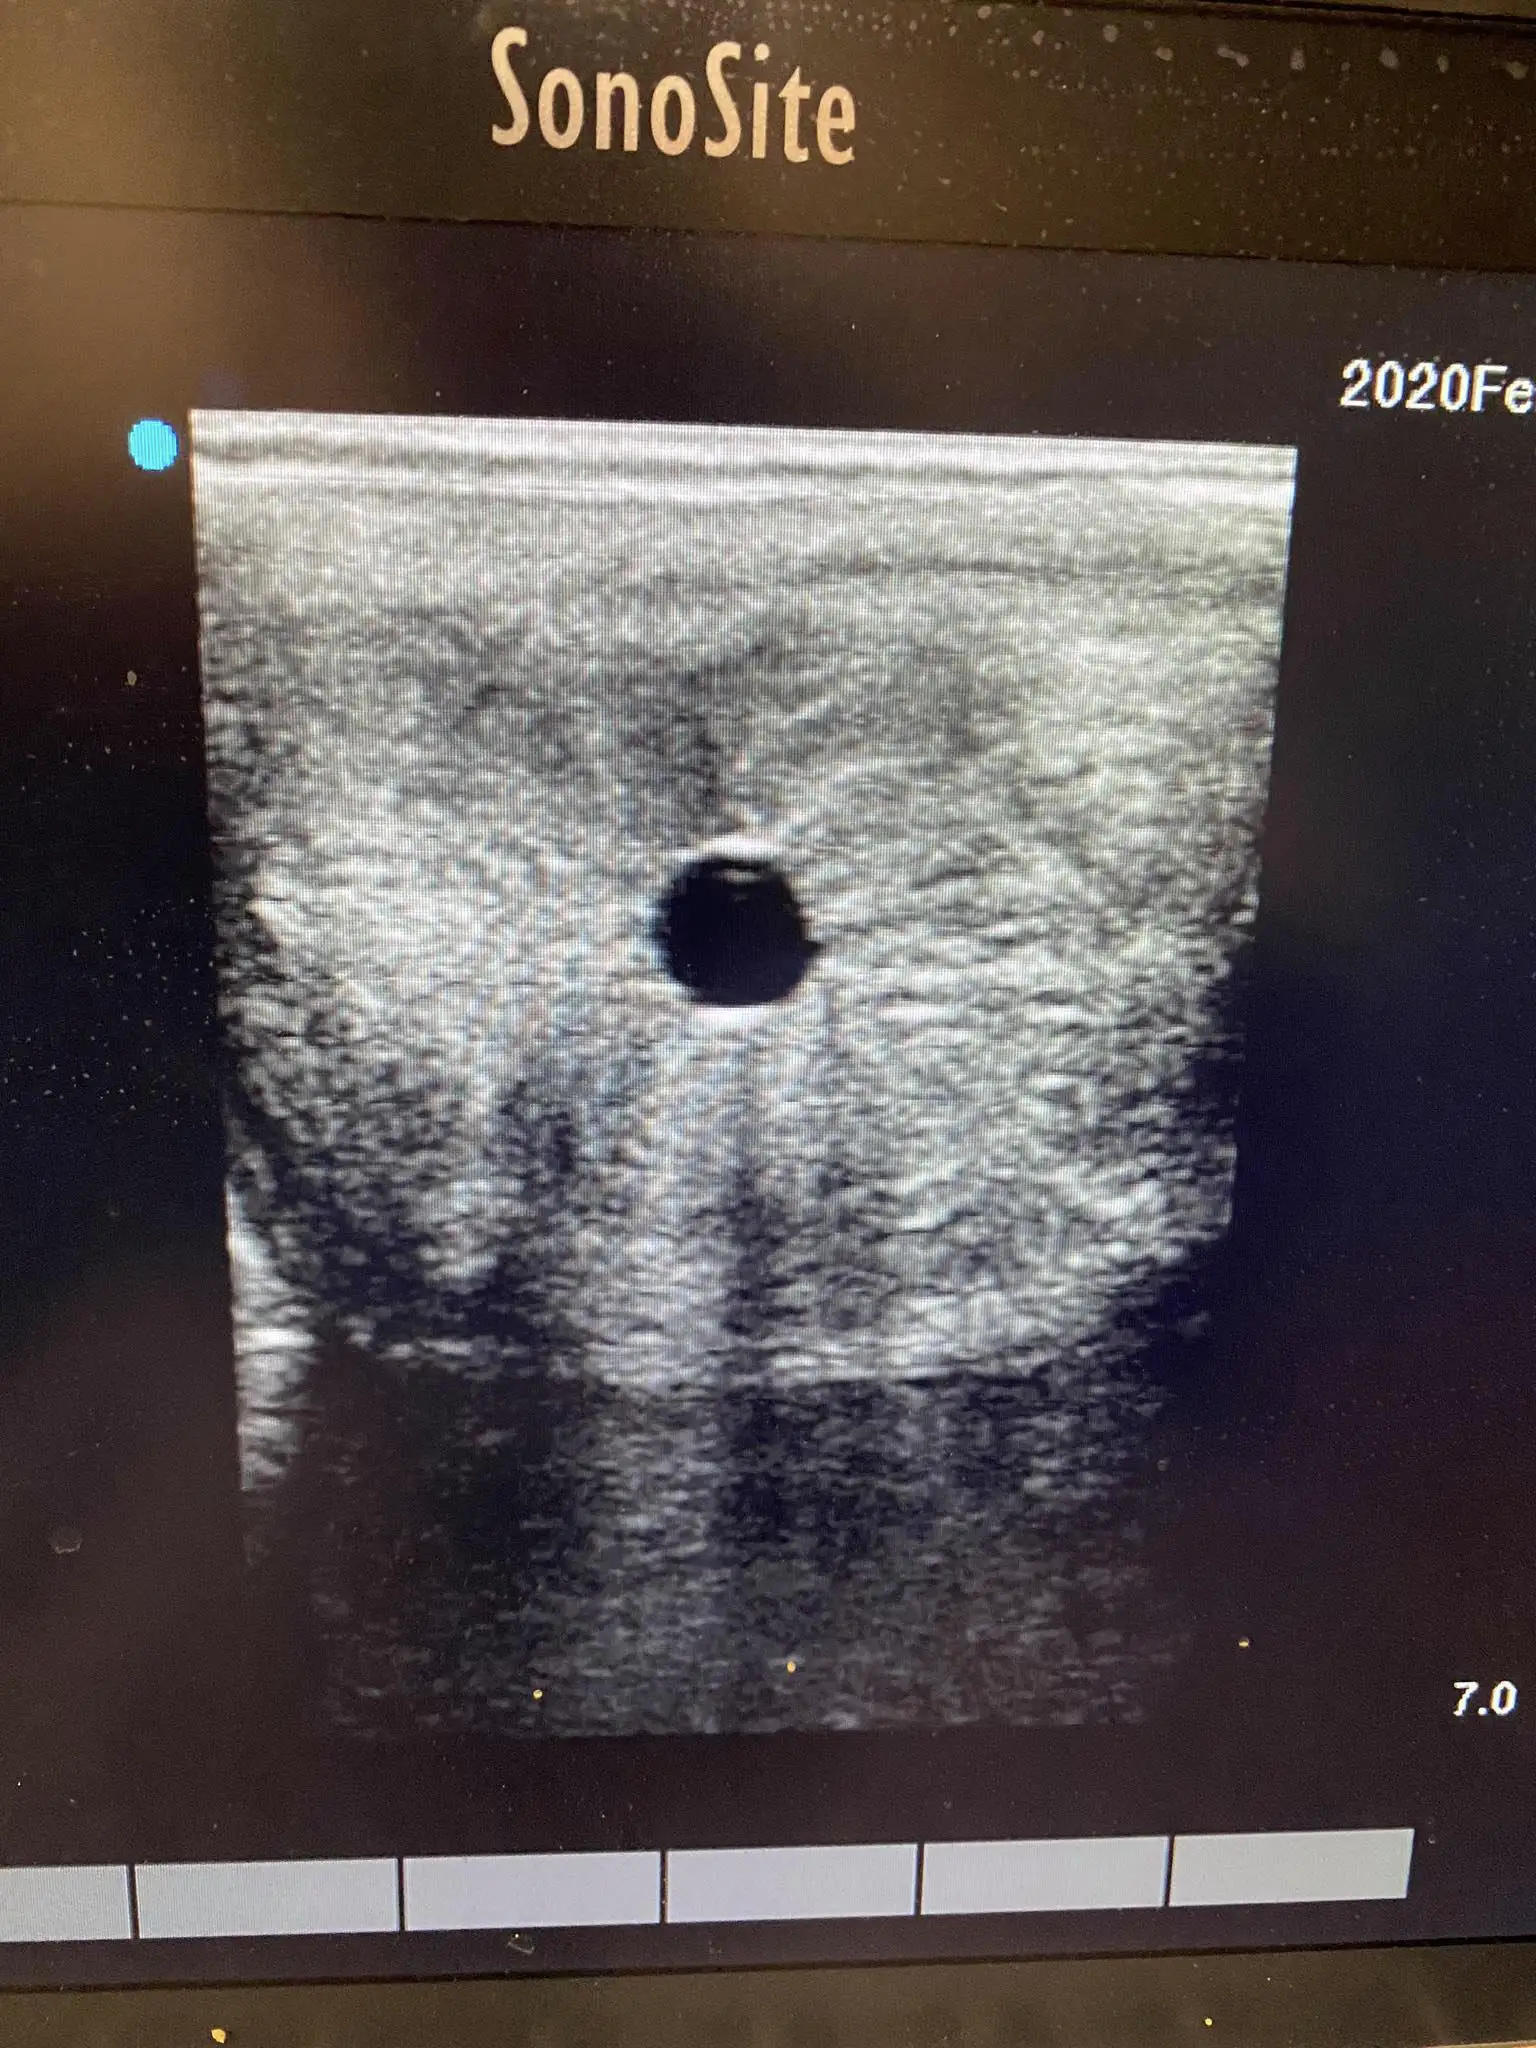

Our digital x-ray and ultrasonography capabilities are second to none, ensuring the best results for diagnosis and prognosis in most cases. Cases ranging from reproductive to medical benefit from both our modern equipment and wide-ranging experience.